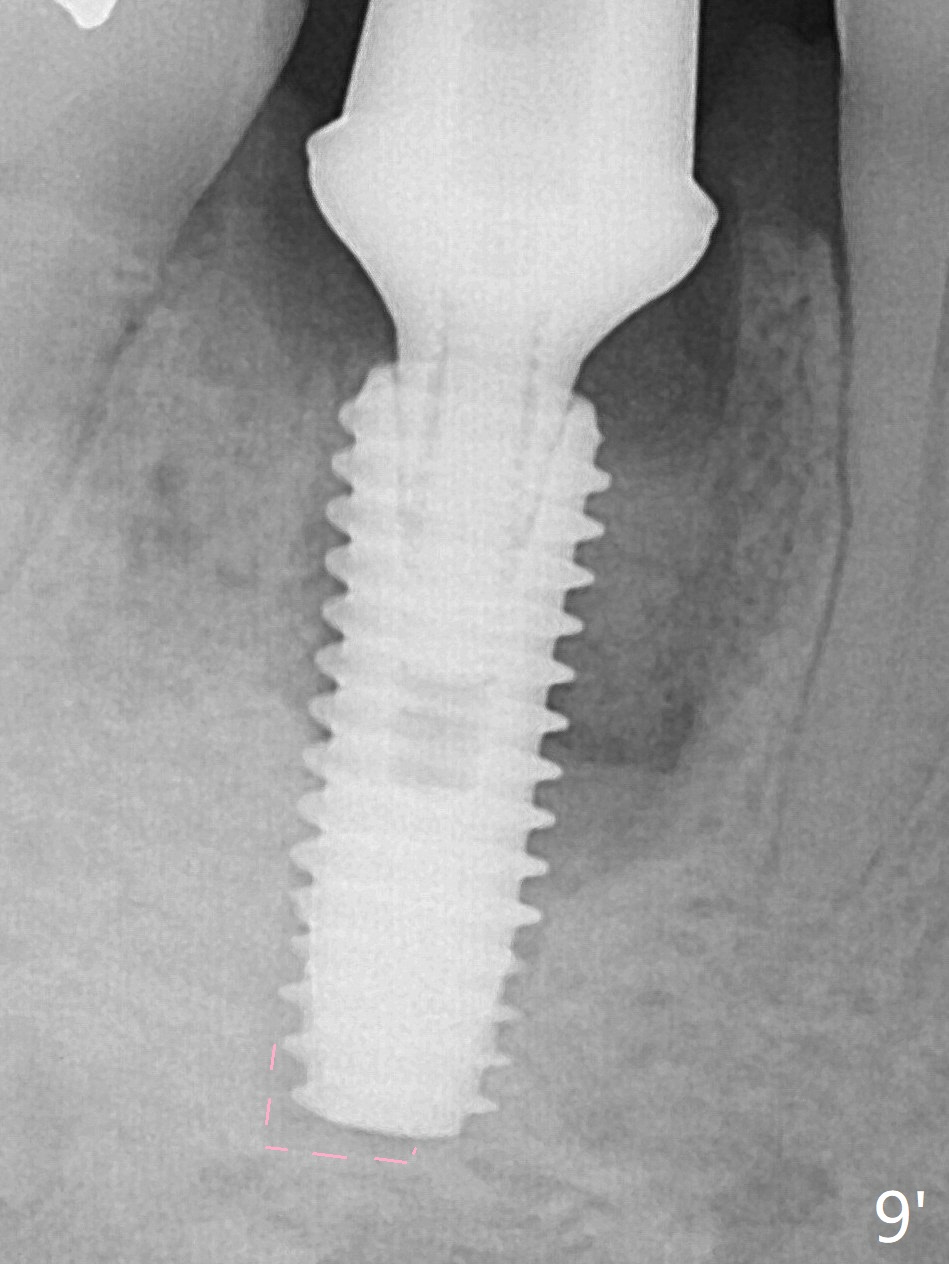

Preop oral Amoxicillin seems to be associated with reduction in the buccal and lingual (Fig.3 arrow) fistulae at #30, but there is mesiobuccal swelling (Fig.1 *) with 7 mm pocket (Fig.2). Osteotomy is initiated in the middle of the septum (Fig.3-5 S). As the osteotomy increases, it shifts mesially (Fig.6 arrow). Guided surgery is able to reduce shifting. A 5x13 mm implant is not seated completely (Fig.7) apparently due to osteotomy shifting. After removal of the bone from the osteotomy distally, the implant remains unseated with lower torque value (Fig.8). Following reuse of the 4.3 mm drill deeper by 1-2 mm, the implant is seated to a satisfactory depth (Fig.9 with increase in torque to 50 Ncm) with placement of Vera Graft (*) and a 7.5x4(3) mm abutment. After a second round of allograft placement (Fig.10 *), the implant is found to be 4 mm from the IAC. At the later stage of osteotomy, the coronal end of the septum is destroyed with loss of osteotomy depth landmark. It is apparent that the soft tissue landmark may be more reliable. The implant threads appear to be covered by the bone graft 3.5 months postop (Fig.11). The abutment is changed to 6.5x5(3) mm one before impression with minor margin prep. The bone density seems to increase 5 months postop, i.e., immediately post cementation (Fig.12) and 10 months postop (5 months post cementation (after retightening abutment), Fig.13 (*)). Periimplantitis develops mesiobuccally, consistent with bone loss 1 year 7 months post cementation (Fig.14 *); the implant seems to have been buccally placed. Bone graft is necessary with PRF or GEM21S if the vein is small and 6-month membrane with a hole around a 7.5x4(4) cemented abutment for easy wound closure. Take 5x5 CM CBCT to determine which wall has defect, buccal or lingual. Check mesial contact. If so, remove the crown, reseat the abutment (possible incomplete seating) and re-impress after bone graft.